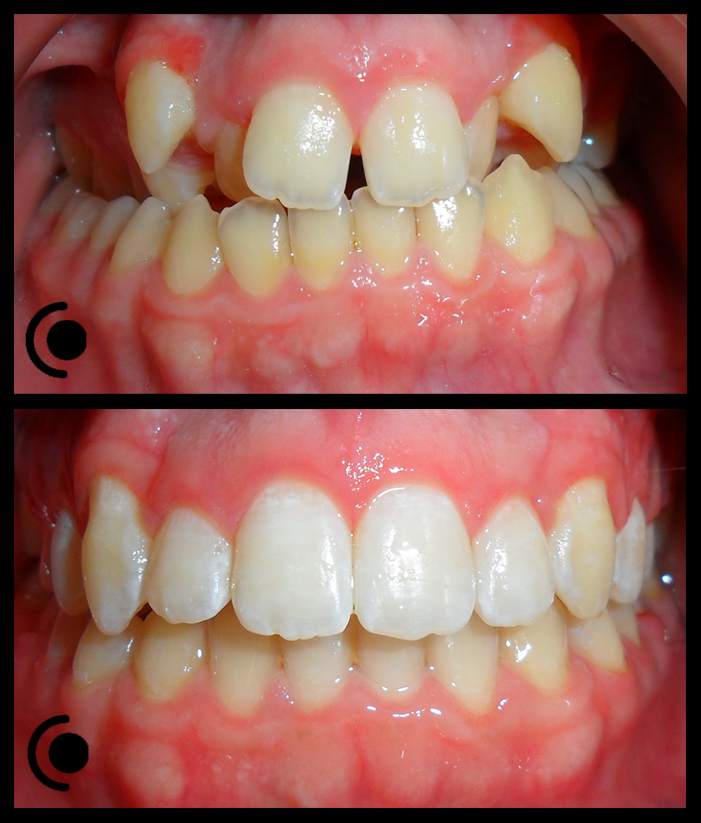

O našoj kvaliteti najbolje govore naši rezultati!

Centar za ortodonciju Petra Džapo